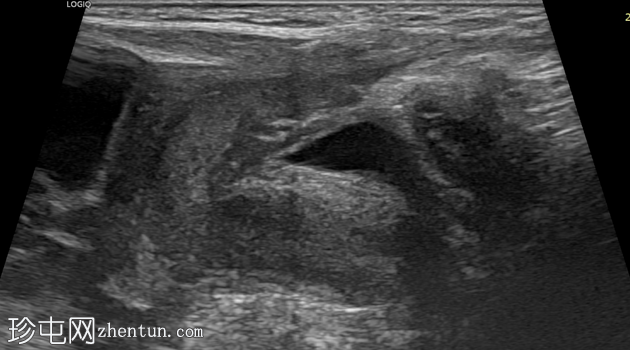

横切面

纵切面

右侧努克氏疝管长约6毫米,内含部分子宫和卵巢(大小约1.5 x 1厘米)。在整个检查过程中,这些组织均保持原位。

对侧附件呈多囊性改变,大小约3 x 1.8厘米。

膀胱外观大致正常。

上述超声特征清晰地显示了努克氏疝管的内容物及其延伸范围;其中包含患者的一侧卵巢和部分子宫组织。

这些特征符合卵巢努克氏疝的诊断。